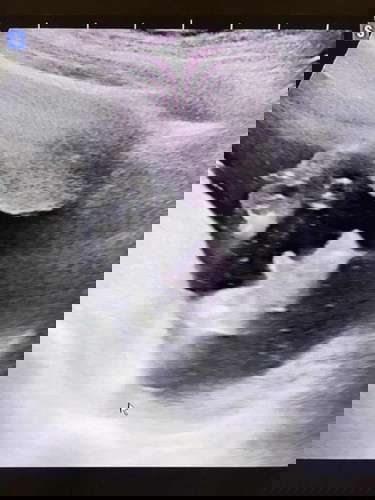

ทีมเพศชายคร้าบ วันนี้ไปเจอหมอ หมอบอกได้ผุ้ชายน้าา👶🥰 สมใจคุณพ่อมากกเลยจร้ 👶🥰

ทีมลูกชายจร้ 4เดือนเเล้วลงพุงมากเลยย🥰😆

บ้านนี้4เดือนป้าหมอบอกผช.เหมือนกันค่ะ น้องนอนคว่ำ แม่ดูไม่ออก😅